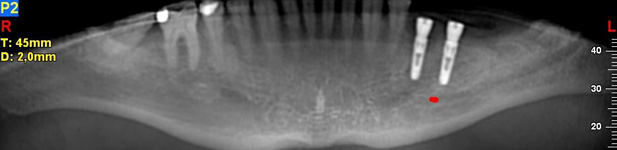

NewTom Implant Planing

Jedná se o plánovací program, který využívá dat získaných při vyšetření pomocí přístroje New Tom. Tento program umožňuje tříprostorovou počítačovou simulaci při plánování pozic implantátů.

Součástí programu je i databáze, ve které mohou být uloženy všechny typy implantátů od všech výrobců, včetně jejich délek, průměrů i tvarů.

Lékař si vytvoří všechny typy zobrazení potřebných pro naplánování – tedy 2D snímky (panoramatický), příčné řezy i 3D model.

Vidí zde i důležité anatomické útvary – čelistní dutinu, průběh nervu atd. Po proměření množství kosti – šířky i výšky vybere z databáze vhodný typ implantátu a umístí ho do požadované lokality.

Ihned vidí jeho pozici ve všech 3 rovinách a na všech snímcích i 3D modelu. Může upravovat podle potřeby jeho pozici, sklon atd.

Všechny vybrané a správně umístěné simulované implantáty se ukládají do „počítačové karty“ pacienta s jejich pozicí, délkou, průměrem, typem i sklonem.

Lékař i pacient tedy ještě před vlastní operací vidí, jak by mělo ošetření probíhat a vypadat.